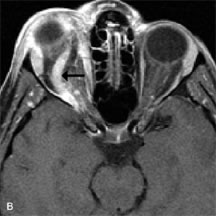

Metastatic Tumors

Breast carcinoma metastatic to the orbit has been demonstrated to be hypointense to the surrounding orbital fat on T1-weighted studies and hyperintense on T2-weighted images and has an affinity to the extraocular muscles (Fig. 20).50,64 The MRI characteristics of prostate carcinoma metastatic to the orbit have been described as involving the greater and lesser wing of the sphenoid, orbital roof, and optic canal. Diffuse bone hypertrophy with isointense or slightly hyperintense tissue on T1-weighted images represents the osteoblastic carcinomatous bone infiltration. Contrast enhancement is variable on T1-weighted and fat-suppressed images.65

Fig. 20. A. T1-weighted MR scan demonstrates nodular enlargement of both medial rectus muscles (arrows). B. T1-weighted fat-suppressed contrast-enhanced scan confirms the presence of small metnstatic deposits within the muscles (open arrows).